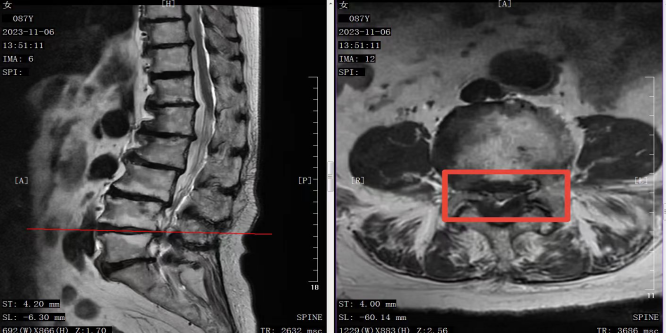

图1 腰椎核磁共振,见腰椎退变严重,腰4-5水平中央椎管重度狭窄,硬膜囊明显受压。